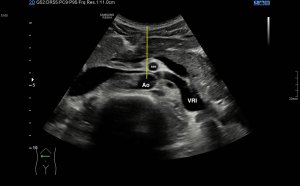

Hoy va de anatomía. ¿Conoces el músculo Digástrico? Es un músculo situado debajo del mentón, es par, uno a cada lado, con dos vientres musculares y un tendón común. El vientre posterior inserta en la mastoides. El anterior en el mentón. Tienen un tendón común ambos vientres, ese tendón común es abrazado por una fibra que a modo de cabestrillo lo envuelve y lo une al Hioides, considerándose por tanto un músculo suprahioideo.

Su función es descender el Maxilar Inferior y elevar el Hioides.